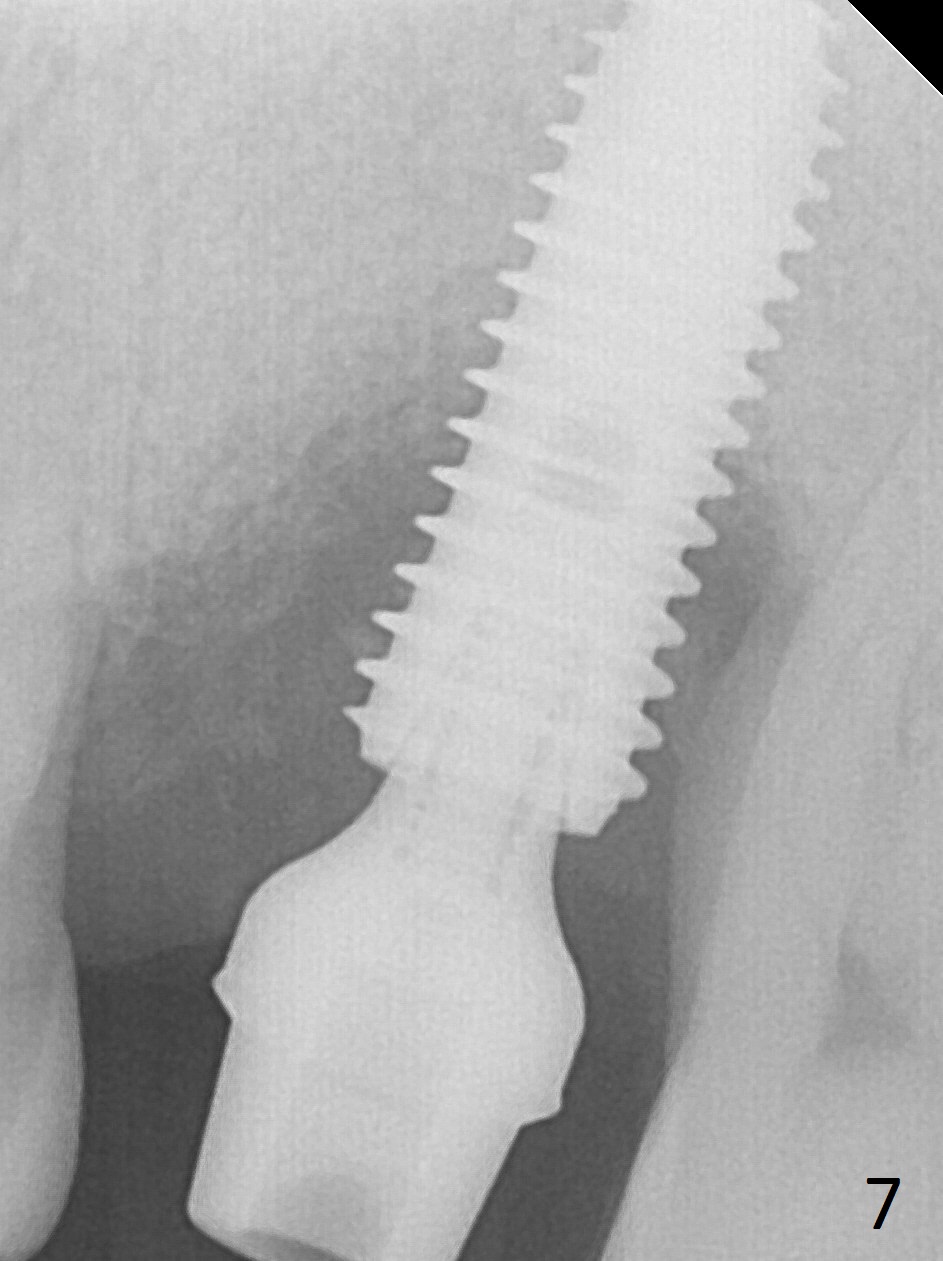

There is severe gingival recession: 15 DB, implant plateau exposure, surrounded by healthy granulation tissue, 3.5 months postop. PA shows #15 + implant osteointegration and bone loss coronally (Fig.7). Afterward, the abutment is changed from 6.5x4(4) to 5.5x5(2) mm with fabrication of a provisional. The patient feels that it is easier to brush with a temporary crown. Model shows gingival recession (Fig.8 G) with implant thread exposure distobuccally (I). Although there is no obvious change in bone regeneration 7.5 months postop (2.5 months post cementation, Fig.9) as compared to Fig.7, there is no more distobuccal gingival recession (data not shown; due to use of Water Pik). To avoid the gingival recession, the implant should have been placed more mesial and deeper (Fig.10 green) with use of a longer-cuff (pink) abutment.